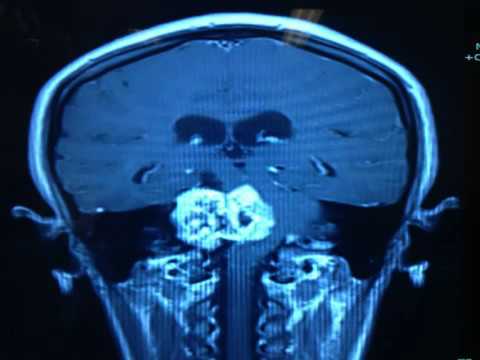

Prof. Dr. Selçuk Yılmazlar, nöroşirürji alanında klinik ve cerrahi uygulamalarıyla ulusal ve uluslararası düzeyde çalışmalar yürütmekte olup, beyin, omurga ve sinir sistemi hastalıklarının tanı ve tedavisinde modern cerrahi yöntemler uygulamaktadır. Uzmanlık alanları arasında beyin tümörleri, bel ve boyun fıtıkları, damar ve sinir cerrahisi gibi birçok alanda hastalarına hizmet sunmaktadır.